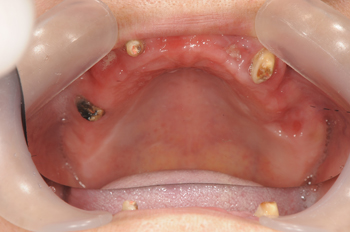

チラシをご覧になって来られた患者様です。入れ歯が合わなく、食事ができないということでall-on-4を希望されてご来院されました。元々受け口で、義歯の見た目も気に入っておられなかったということなので、審美面についてもご相談しながら治療方針を決めていきました。

Before

マグネットデンチャーにも興味を持っておられましたが、全体的に進んだ歯周病の状態や、将来的なことを考え、all-on-4での治療を行う事なりました。歯を調整することにより、受け口も目立たなくなり、食事も取れるように術後に調整していきました。